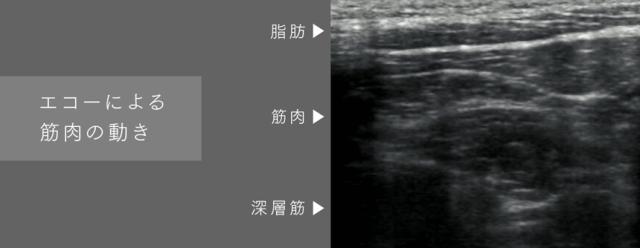

"EMS"で首まわりの硬まりがちな筋肉を緩めながら休ませます。

独自のテクノロジーにより生まれた3種類のEMSモードと20段階のレベル調整が可能。2Hz〜85HzのEMSにより固まりがちな筋肉を緩めながら休ませます。